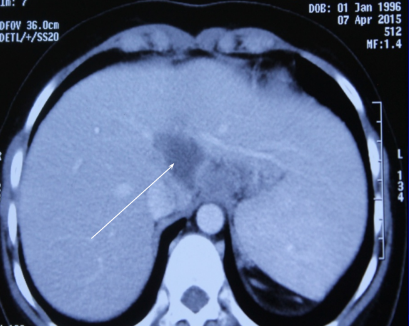

| Khối lao gan được phát hiện trên nữ sinh bị mắc Wilson. Ảnh: Bác sĩ cung cấp. |

Thông qua các xét nghiệm về đột biến gen, nữ sinh được chẩn đoán bị bệnh Wilson. Sau 18 tháng điều trị, mọi thứ trong cơ thể Ngoan được trở lại bình thường, kể cả kinh nguyệt. Nhưng vài tháng sau đó, khi siêu âm bụng, các bác sĩ phát hiện một khối u ở gan đường kính 30 mm, do gan nghèo oxy, xảy ra trên cơ địa suy giảm miễn dịch.